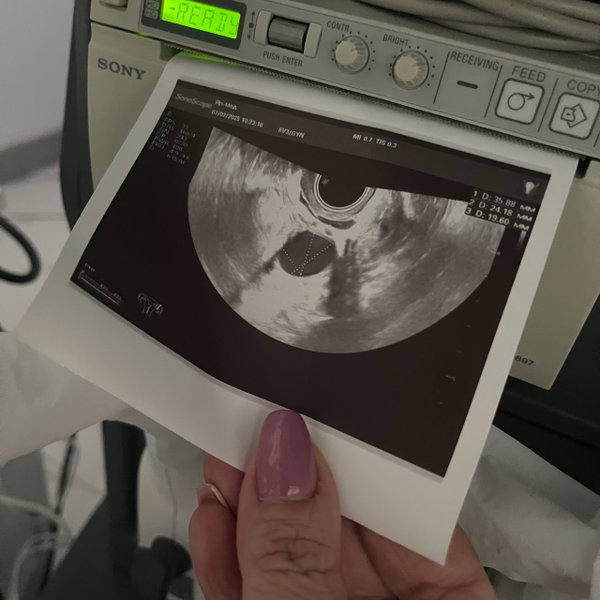

Кажется, еще вчера тест показал две полоски, а сегодня мы уже рассматривали ручки и ножки на мониторе ВАШЕ крошечное солнышко‼️ PS.. группа поддержки в виде ️бабушки и мужа на осмотре . были --- Бородулина Наталья (Врач УЗИ, Косметология) (08.01.2026): Давайте поиграем‼️ Угадайте по фото #УЗИ, кто тут ( Шутка, конечно, рано еще Но верить в чудеса можно уже сейчас). Поделитесь в комментариях своими первыми #фото «горошков», «фасолинок» и «эмбриончиков» устроим галерею самого начала жизни ️

УЗИ диагностика 8, 9 и 10 января‼️ Запись по телефону: ️для Самостоятельных ️ запись по кнопке ЗАПИСАТЬСЯ ⤵️ --- Бородулина Наталья (Врач УЗИ, Косметология) (06.01.2026): #Сочельник… время чудес вы уже загадали заветное желание ⁉️ На небе разглядели первую звезду? На фото УЗИ 4 недель а если подключить фантазию, что видите? Я вижу малыша, который держит шарик С Сочельником вас, дорогие мои‼️ И с наступающим Рождеством по беременности можно с мужем ️

Давайте поиграем‼️

Угадайте по фото #УЗИ, кто тут ( Шутка, конечно, рано еще Но верить в чудеса можно уже сейчас).

Поделитесь в комментариях своими первыми

#фото «горошков», «фасолинок» и «эмбриончиков» устроим галерею самого начала жизни ️

#Сочельник… время чудес вы уже загадали заветное желание ⁉️ На небе разглядели первую звезду?

На фото УЗИ 4 недель а если подключить фантазию, что видите? Я вижу малыша, который держит шарик